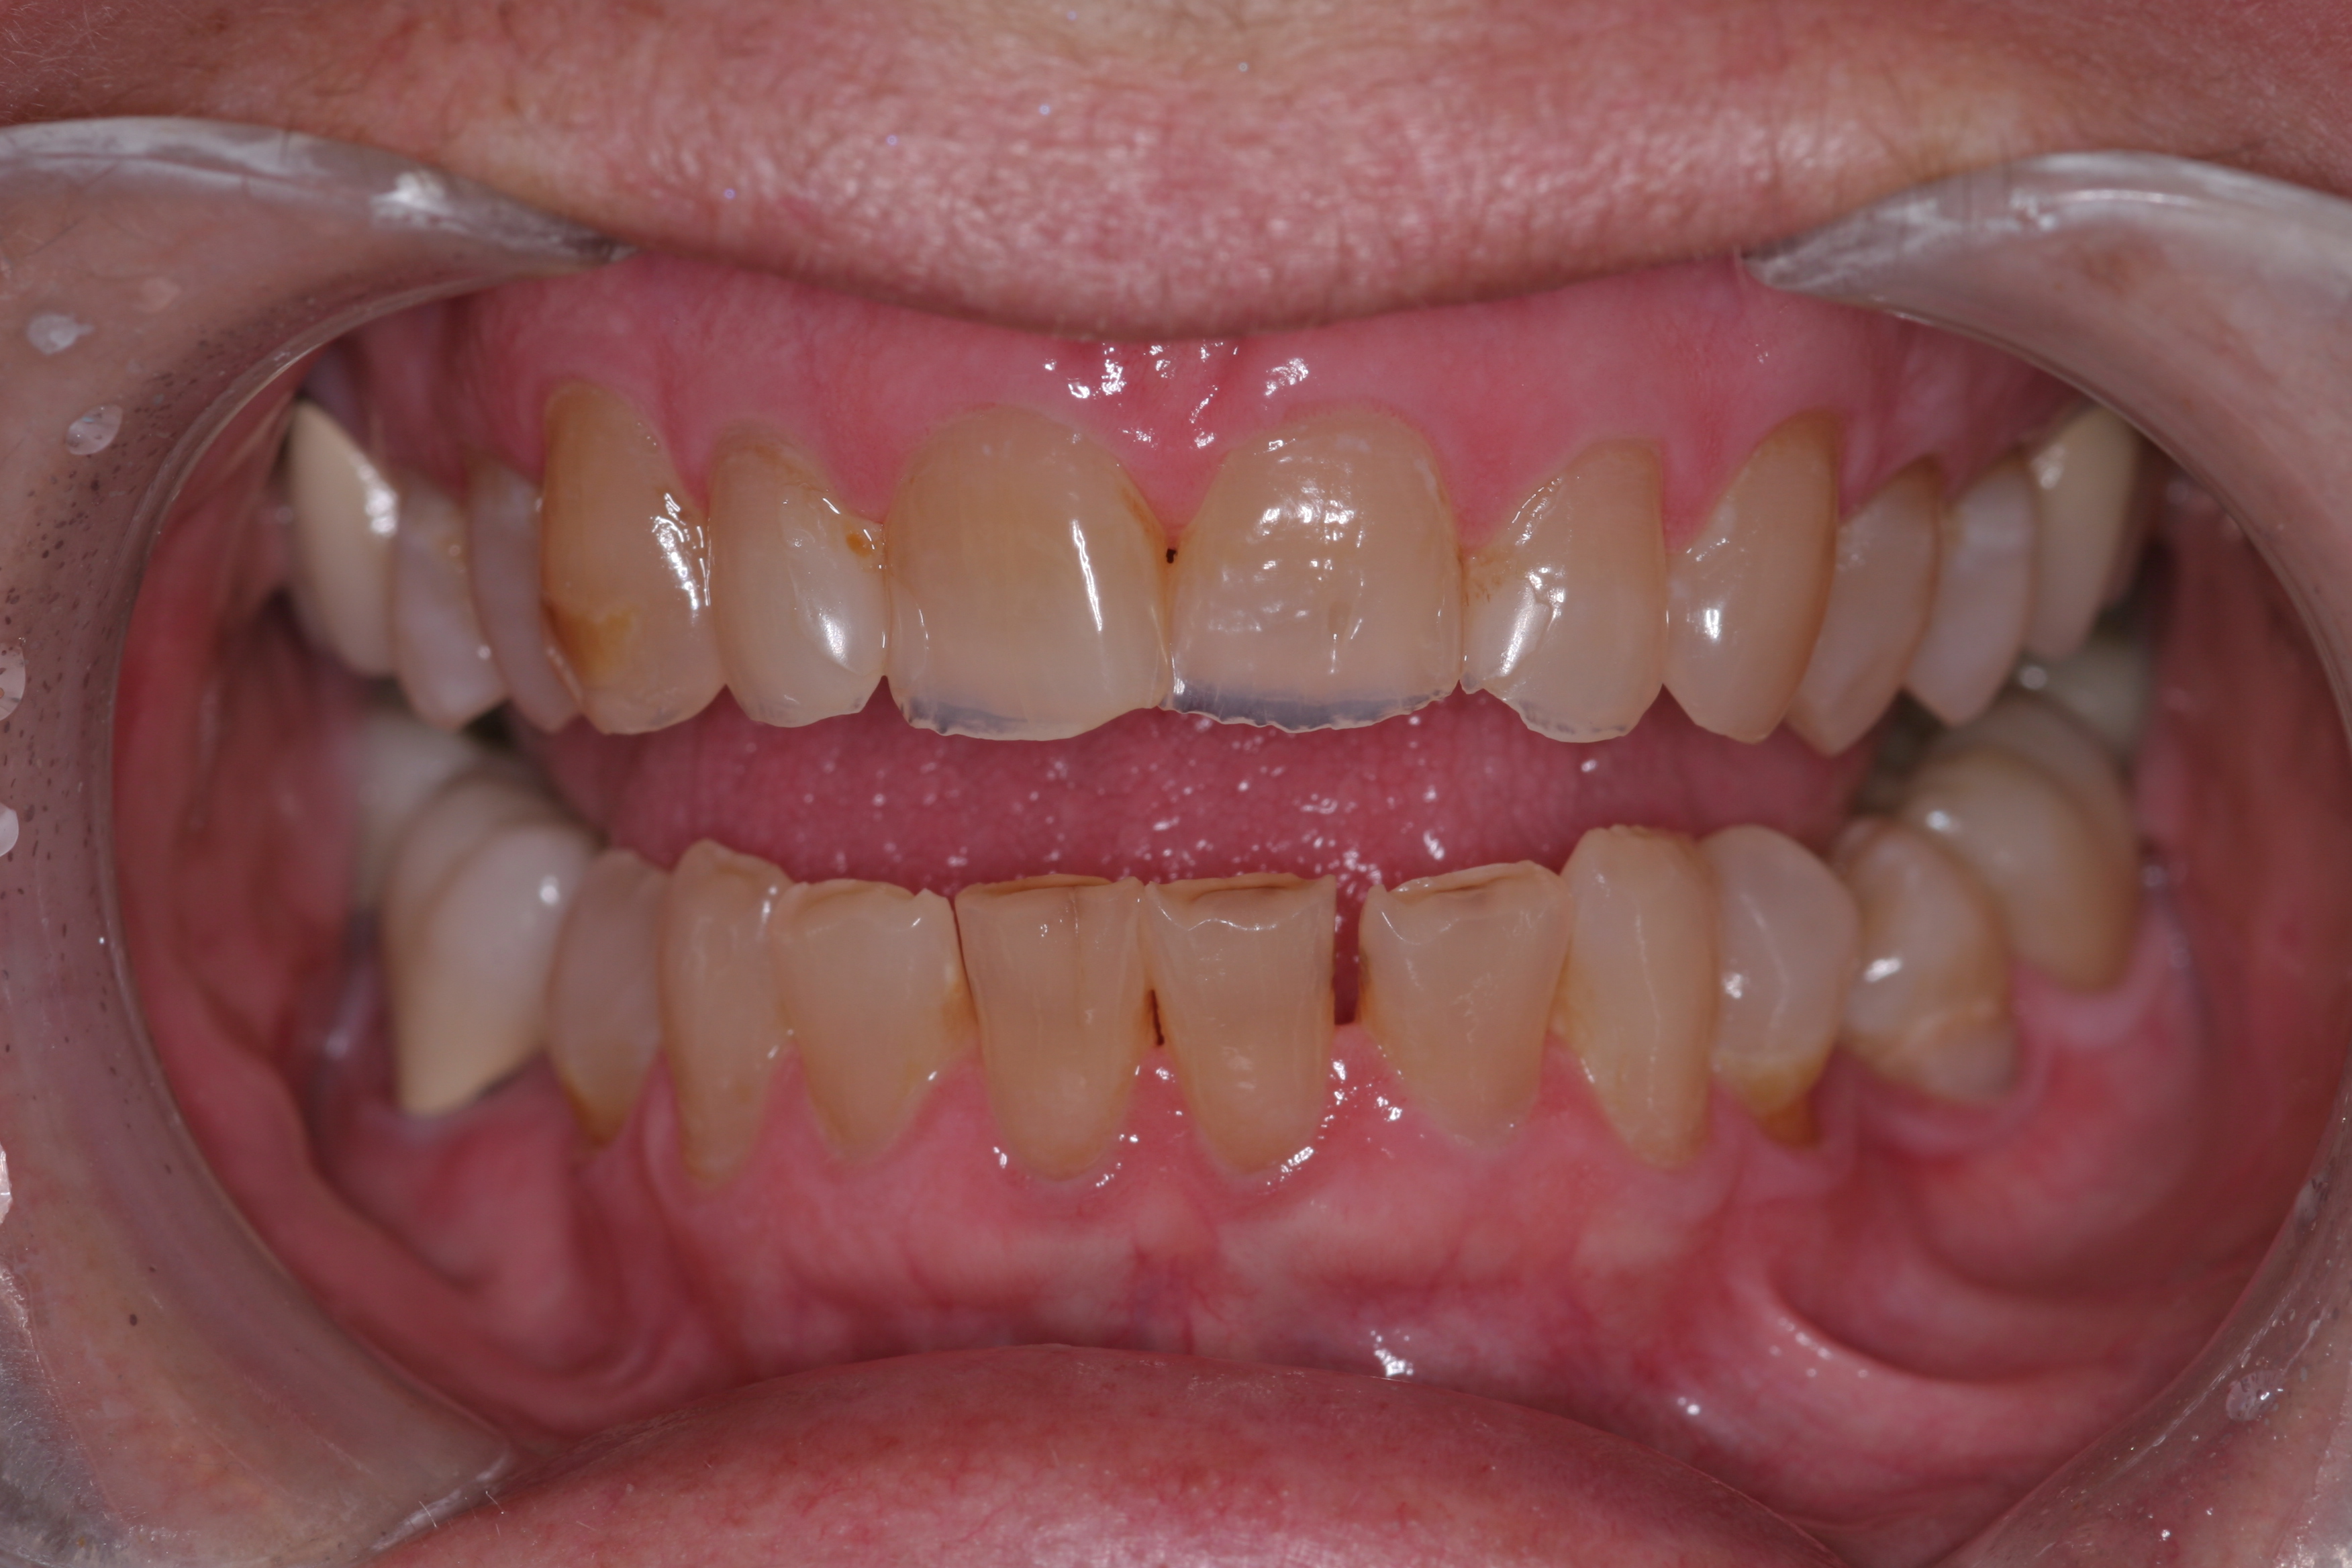

(9.) This patient has lost nearly 40% to 50% of his maxillary anterior tooth structure, yet the teeth are still in full intercuspation due to continued eruption as tooth structure is lost due to wear.

Figure 9

For instance, the patient in Figure 9 has lost nearly 40% to 50% of his maxillary anterior tooth structure, yet the teeth are still in full intercuspation due to continued eruption as tooth structure is lost due to wear. As wear occurs on the lingual aspects of maxillary anterior teeth, teeth drift to the lingual, which constricts the envelope of function. Wear on the lower incisors can lead to super eruption, which increases the overjet/overbite relationship. Both of these alterations in tooth position steepen the anterior guidance and are less than desirable situations with patients with worn dentitions.